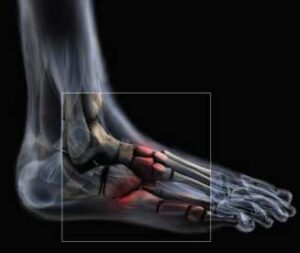

Die Orthopädie ist ein medizinisches Fachgebiet, das sich mit der Prävention, Diagnose und Behandlung von Erkrankungen und Verletzungen des Bewegungsapparates beschäftigt. Knochen, Gelenke, Muskeln, Sehnen und Bänder müssen gemeinsam funktionieren, um uns Beweglichkeit und Stabilität zu ermöglichen.

Auf unserer Seite finden Sie umfangreiche Informationen zu orthopädischen Beschwerden und Erkrankungen. Von der Arthrose über Bandscheibenvorfälle bis hin zu Kreuzbandriss und weiteren Sportverletzungen: wir geben Ihnen einen Überblick über die häufigsten orthopädischen Krankheitsbilder, wie sie behandelt werden können und inwieweit ein Bildgebungsverfahren, wie eine (z.B. MRT Knie, Rücken MRT) bei der Diagnose bei der Diagnose unterstützend wirken können.

Viele Betroffene suchen online nach den Ursachen oder Behandlungsmöglichkeiten von Rückenschmerzen, Bänderriss am Fuß oder Bandscheibenvorfall. Einige der orthopädische Beschwerden oder Verletzungen benötigen zu Behandlung eine Bildgebung und Therapie. Alle relevanten Informationen lesen Sie in den jeweiligen Beiträgen.